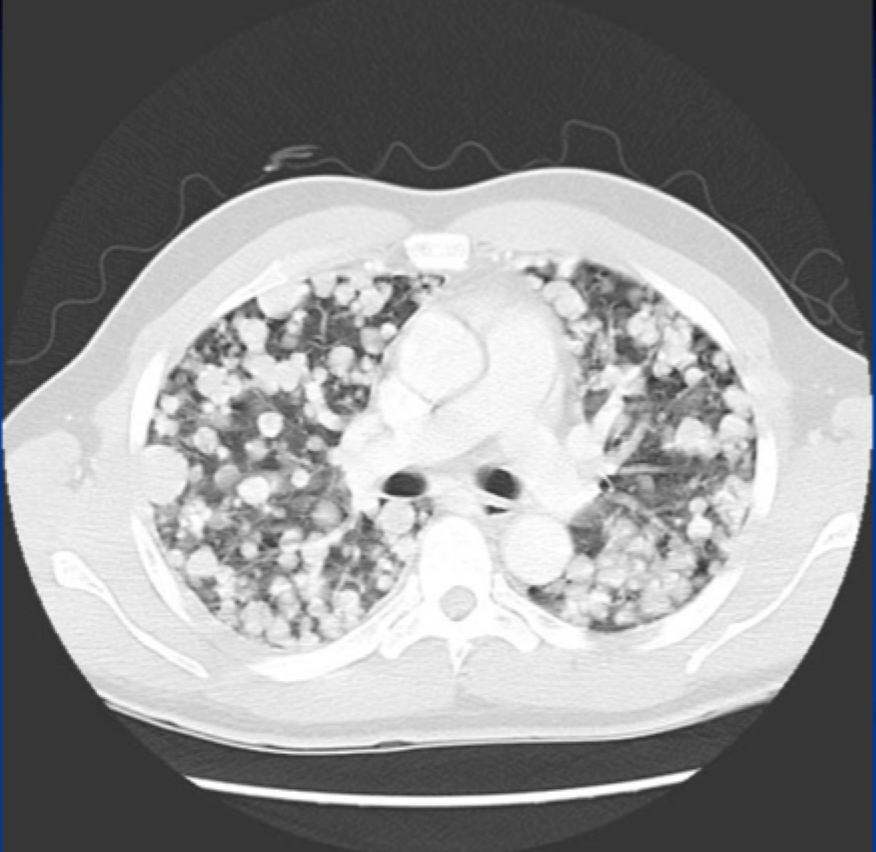

Q

?

A

CT: metastatic lung cancer**

CT is more sensitve …………….

Cannonball lesions = metastatic lung cancer

- multiple spherical densities with sharp margins

-MC: lower lung zones

MC = ASYMPTOMATIC

May present with:

-Cough, hemoptysis

-Dyspnea and hypoxemia (advanced)

-Symptoms are more often referable to the site of the PRIMARY tumor